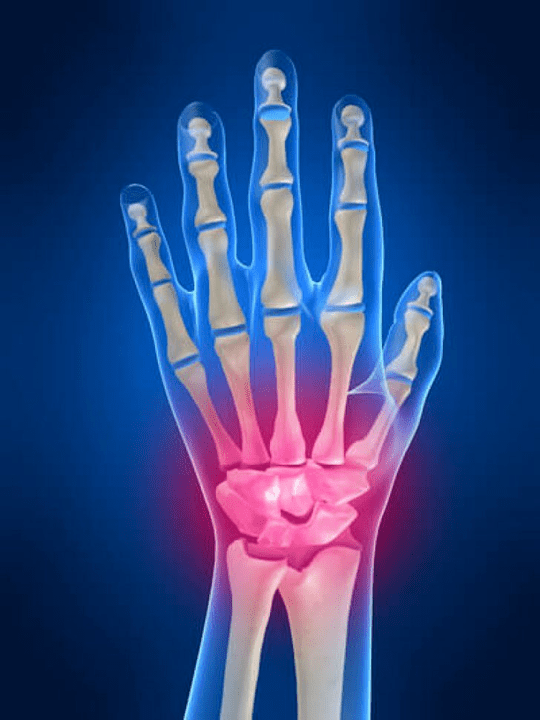

Dolore articolare Le dita sono un segno indispensabile di una patologia comune in cui i componenti strutturali di questi composti sono danneggiati. In primo luogo, il dolore nell'area di queste articolazioni può essere associato a varie malattie autoimmuni (Specini rossi sistemici, artrite reumatoide, artrite della psoriasi, ecc.) in cui i fattori immunitari danneggiano il proprio tessuto articolare.

Il prossimo motivo principale che può iniziare Dolore Ci possono essere lesioni nel cazzo delle dita (Lividi, trasferimenti, ossa rotte, legamenti). Il dolore in queste articolazioni può anche essere provocato da cambiamenti degenerativi nei loro tessuti articolari. Questo può essere spesso osservato nell'osteoartrite.

Le cause del dolore nelle articolazioni delle mani e delle dita

La parte principale secondo le ragioni che causano dolore alla mano e alle dita è occupato da lesioni meccaniche (Fratture, trasferimenti, lividi, ecc.) e malattie autoimmuni sistemiche (Artrite reumatoide, eritematodi di lupus sistemico, psoriasi ecc.). Oltre a queste cause, il dolore nelle associazioni delle mani può causare malattie associate a disturbi metabolici (Ad esempio Gout, osteoartrosi).

Ci sono le seguenti cause principali che causano dolore alle articolazioni della mano e del dito: